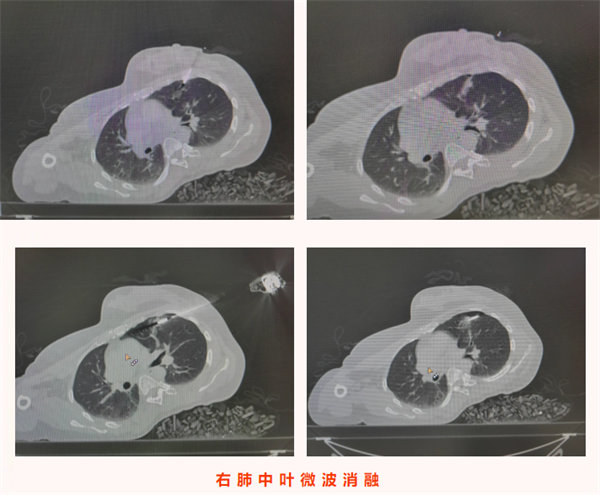

入院后,醫療團隊結合患者既往腺樣囊性癌病史、影像學檢查結果,術前綜合評估后高度懷疑雙側肺結節為腫瘤轉移灶。考慮到患者無明顯癥狀、病灶相對局限,為最大限度減少患者創傷、避免二次手術,團隊決定為其同期實施雙側肺結節診療手術——即CT引導下經皮左肺上葉微小結節穿刺活檢+微波消融術,同期對右肺結節行微波消融術。手術由科主任陳瑜主刀,副主任吳明君擔任助手,魏寶、張寶軍為第二助手。手術過程中,醫師團隊首先聚焦左肺上葉僅0.8cm×0.5cm的微小實性結節,在左側腋下及前外側胸壁精準標記,在患者平靜呼吸狀態下通過CT反復掃描確認穿刺參數,成功獲取活檢組織。并按計劃對左肺穿刺后的結節及右肺斜裂結節同期實施微波消融術,精準破壞雙側病灶組織。整個手術過程一氣呵成,同期完成雙側病灶診療,術中患者生命體征始終平穩。

術后,患者安返病房,生命體征穩定,無胸痛、咯血、氣胸等不適癥狀,飲食睡眠恢復良好。術后病理結果回報,明確左肺上葉結節為腺樣囊性癌轉移灶,與術前評估判斷一致,為后續診療方案制定提供了金標準依據。本例患者無任何癥狀,正是通過定期復查實現轉移病灶的早期發現;同時彰顯了“診斷+治療”一體化微創技術的臨床價值,為惡性腫瘤轉移灶的早期干預提供了高效、精準的診療范式,有力保障了腫瘤患者的長期生存質量。